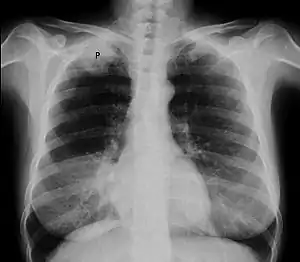

Chest radiograph showing a Pancoast tumor (labeled as P, non-small cell lung carcinoma, right lung), from a 47-year-old female smoker. | |